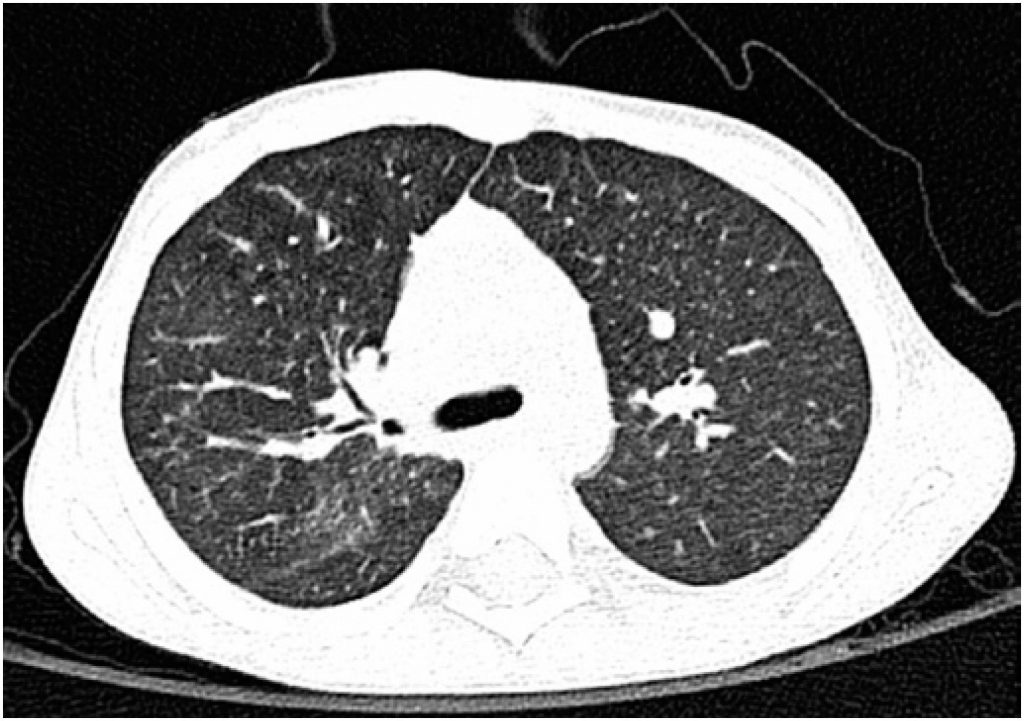

A hemossiderose pulmonar idiopática é uma doença potencialmente fatal que cursa com episódios de hemorragia alveolar de etiologia desconhecida. As manifestações clínicas são variadas, e a anemia pode constituir o único sinal de doença, precedendo em vários meses os outros sinais e sintomas. Apresenta-se o caso de criança de 4 anos, com febre, vômitos e prostração, associados à palidez. Apresentava anemia microcítica e hipocrômica, refratária à terapêutica com ferro. A hipótese diagnóstica de sangramento gastrintestinal foi excluída, após investigação etiológica extensa, inconclusiva. Posteriormente, em radiografia torácica, foram observados infiltrados sugestivos de hemorragia alveolar. O exame citológico do lavado broncoalveolar mostrou macrófagos com depósitos de hemossiderina. Após estudo etiológico, assumiu-se, por exclusão, o diagnóstico de hemossiderose pulmonar idiopática. Foi iniciada terapêutica com corticoides, associada posteriormente a imunossupressor, com correção subsequente da anemia e do padrão radiológico, encontrando-se, atualmente, assintomático.